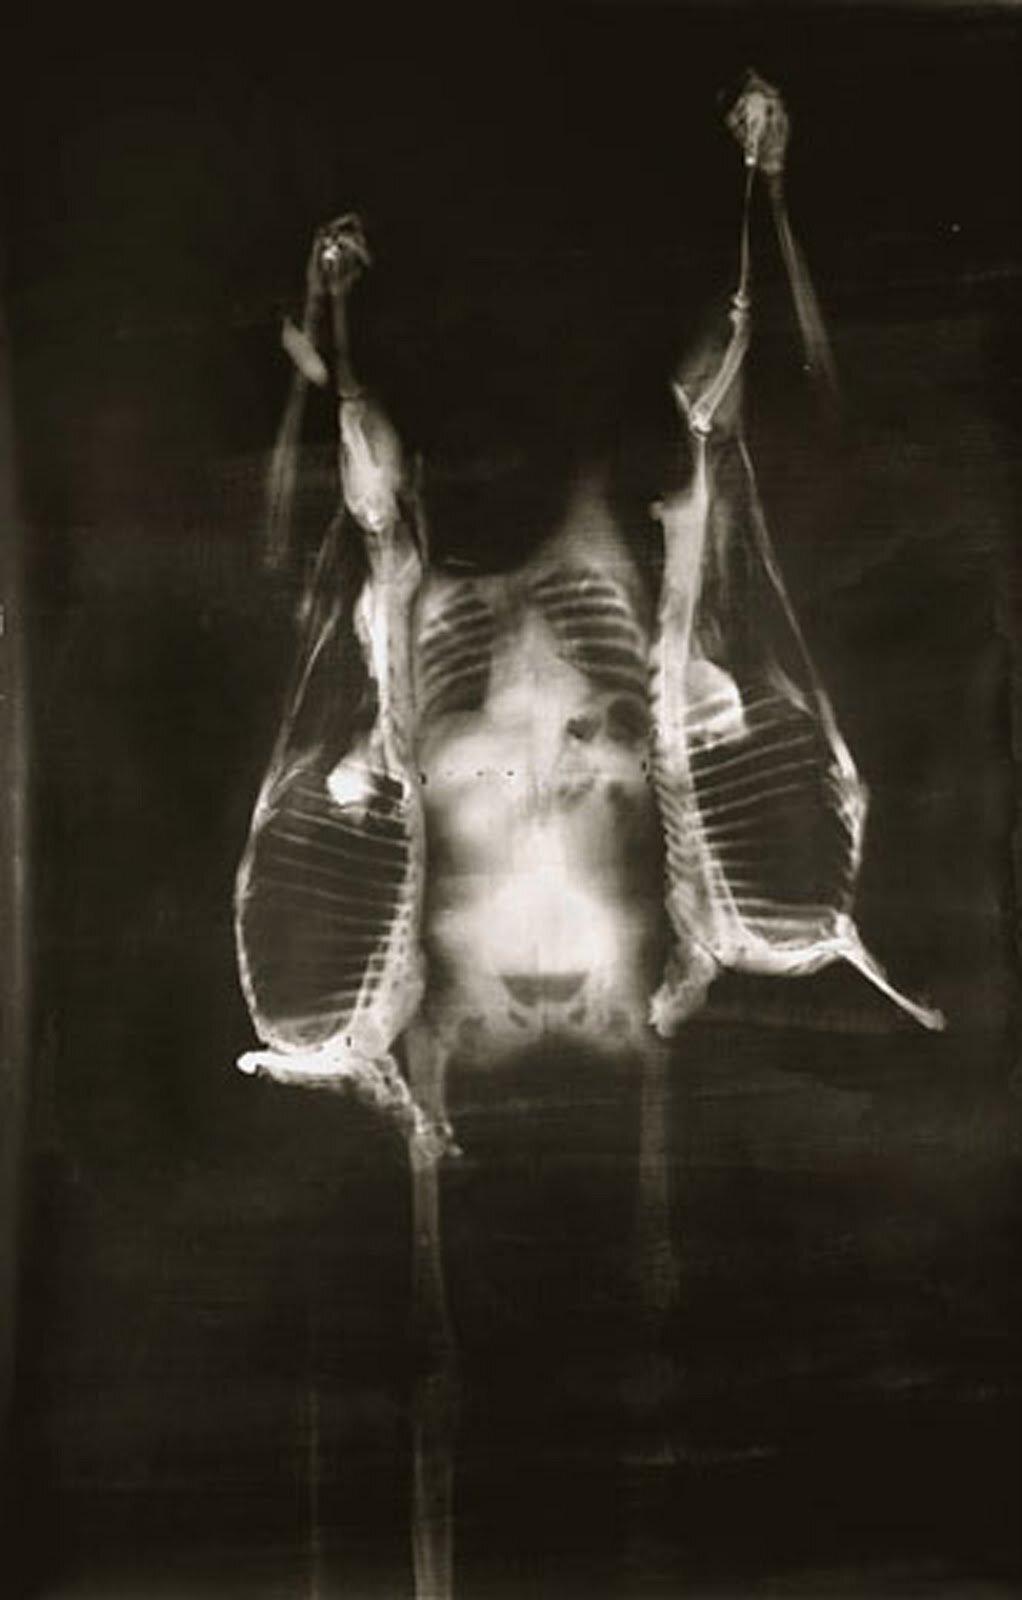

Рентгеновский эффект создает фантастические композиции в этих фотографиях девушки, чье тело становится прозрачным, демонстрируя скелет и внутренние органы. Она позирует в разных позах, ее силуэт светится загадочным свечением. Каждый кадр передает атмосферу научной фантастики и медицинского искусства. Ее кожа кажется полупрозрачной, позволяя увидеть кости и мышцы. Фотографии рассказывают о хрупкости человеческого тела и его внутренней красоте. Девушка то стоит в задумчивости, то делает грациозное движение. Эти иллюстрации вдохновляют на размышления о человеческой анатомии и уязвимости. Каждая картинка - это момент прозрения, когда внешнее уступает место внутреннему. Девушка воплощает образ современной Медузы, сочетающей красоту и загадочность.